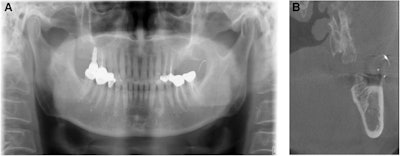

(A) Panoramic radiograph reveals needle fragment located at the anterior ramus of the left mandible. (B) A CBCT image of the lost needle, with two injection needles used as reference points.In this case, the man's dentist referred him to the maxillofacial and oral surgery department to have a suture needle removed from his left buccal mucosa. The needle was supposed to be tied with nylon, but the dentist cut it while performing explantation and local flap surgeries due to the man's chronic peri-implantitis, they wrote.

(A) Photo of single needle fragment lodged in the buccal mucosa. (B) The retrieved suture needle.After the retrieval, x-rays were taken, which confirmed that the broken needle had been removed completely. One week after the removal procedure, the stitches were removed. The patient was healing and experienced no complications.